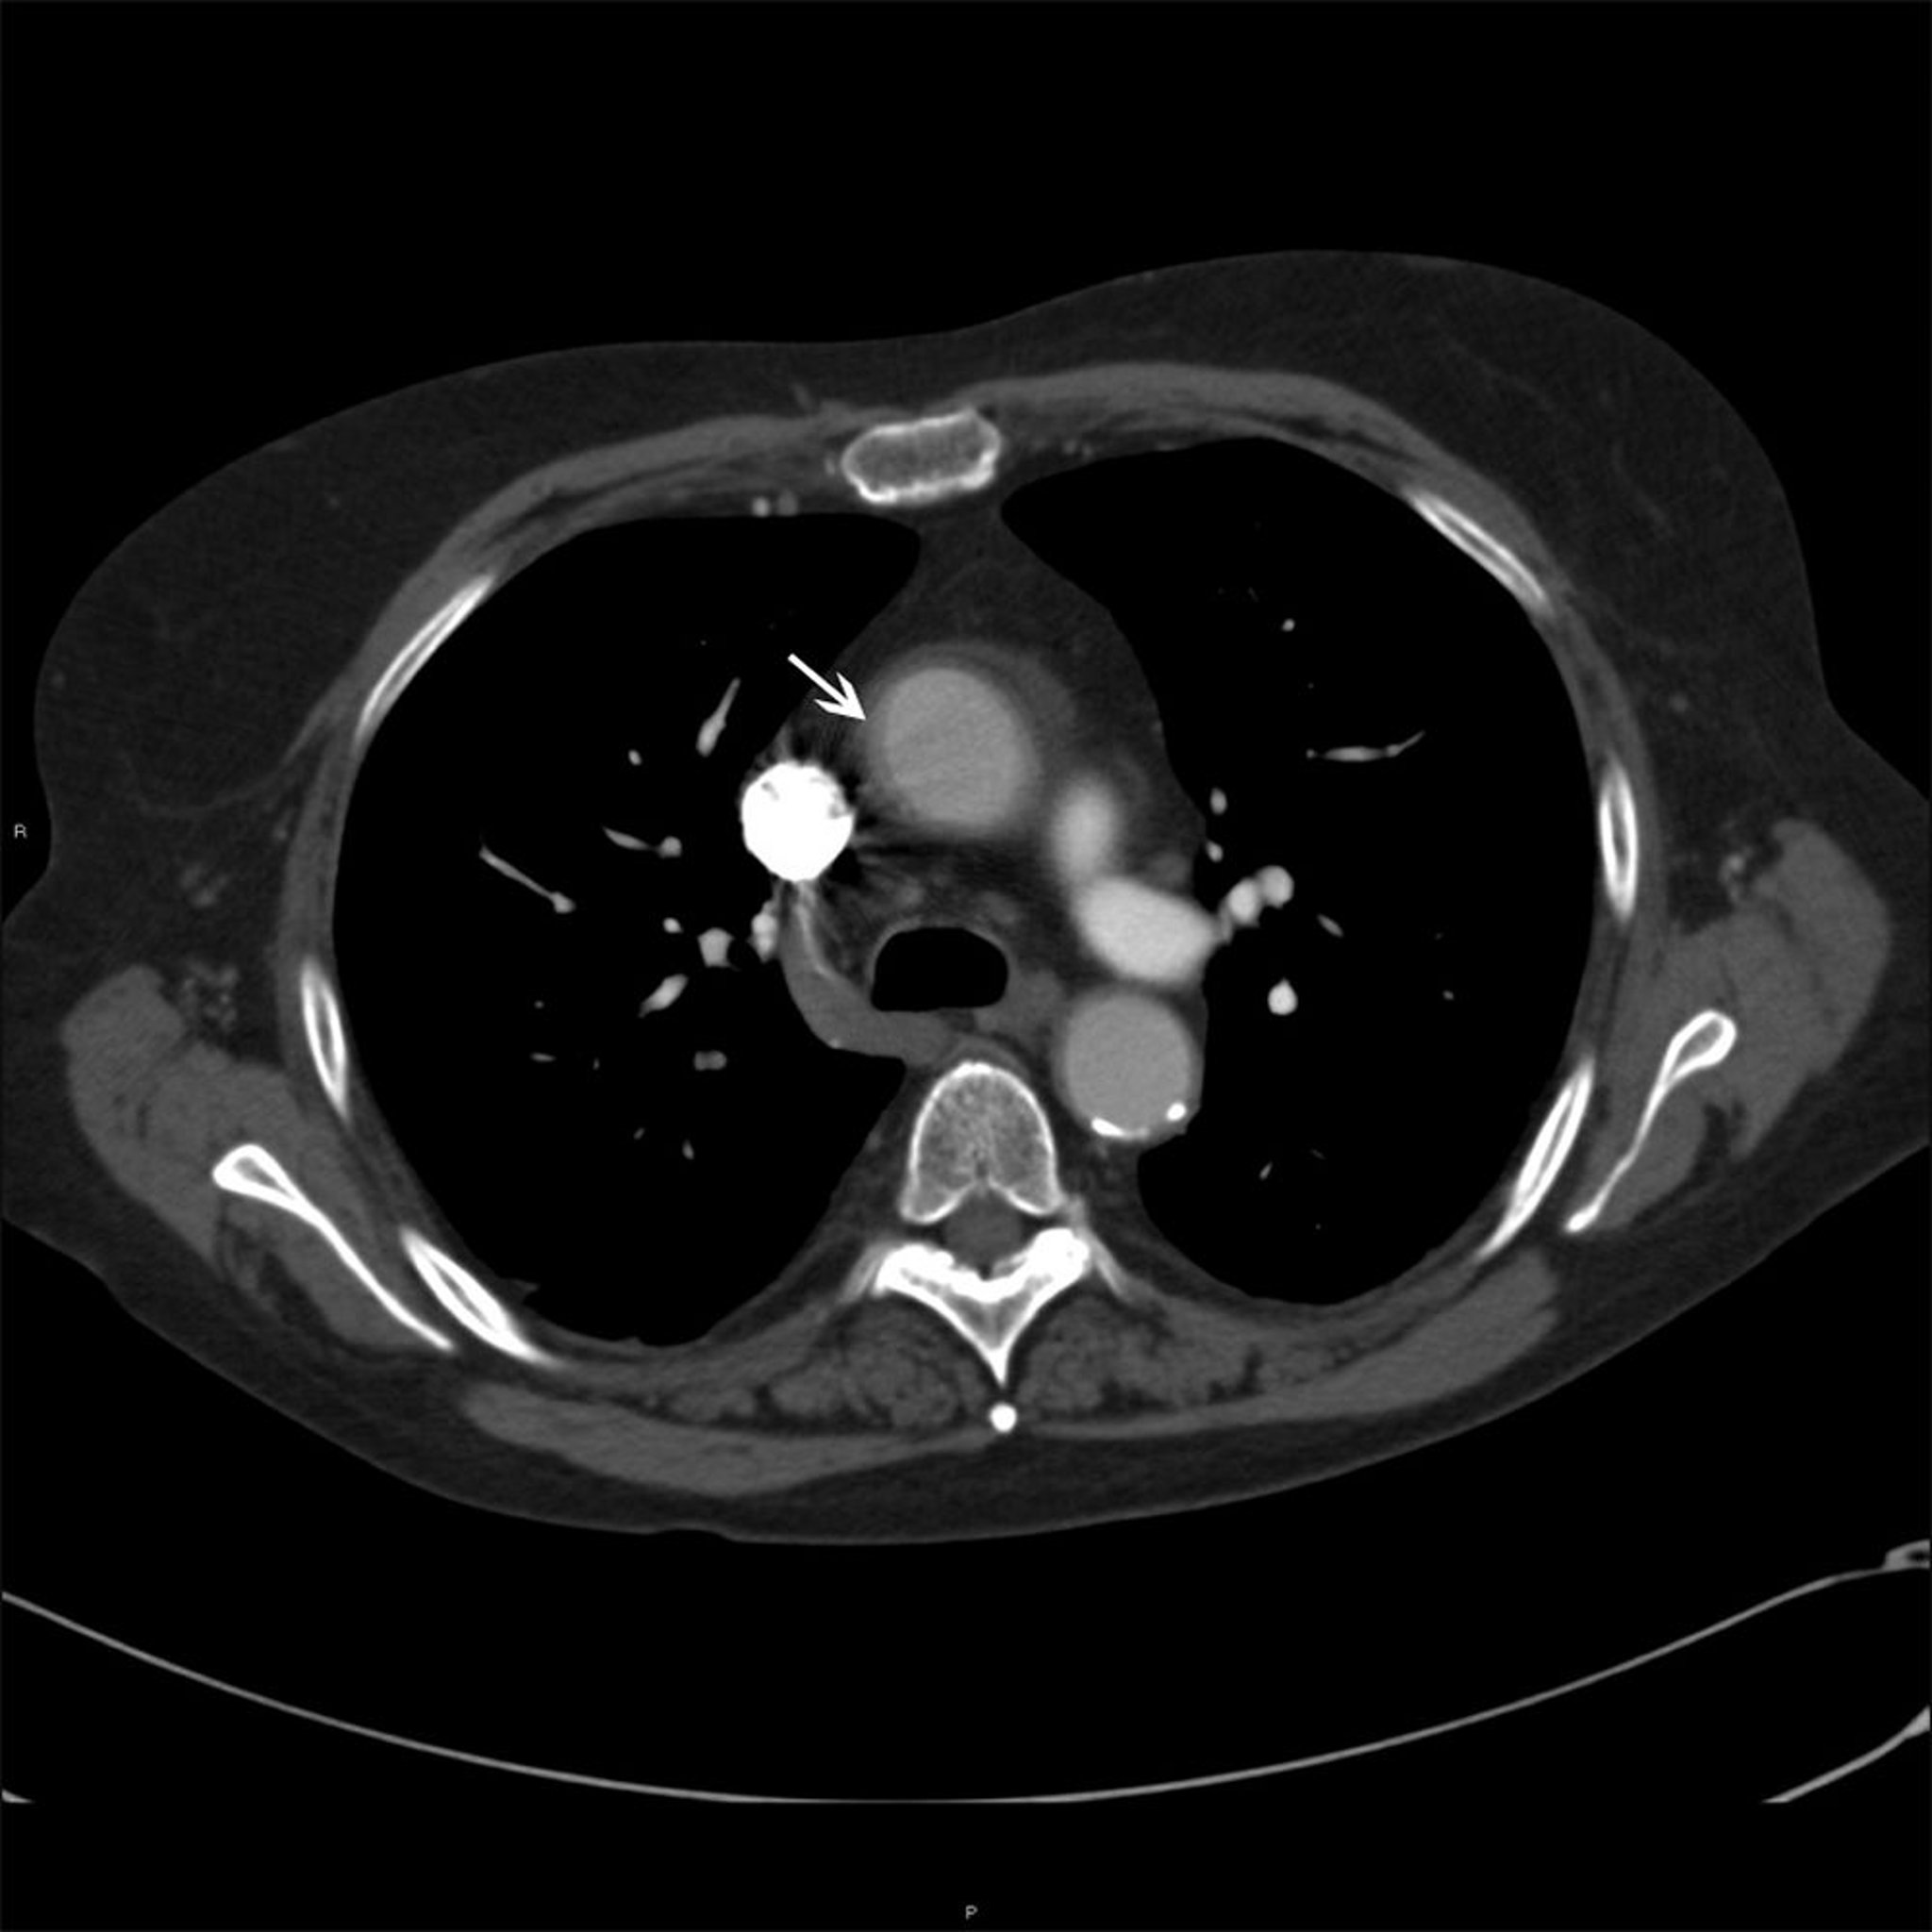

Aorta ascendente in un paziente con arterite di Takayasu

Questa foto mostra l'ispessimento murale (freccia bianca) dell'aorta ascendente in un paziente con arterite di Takayasu.